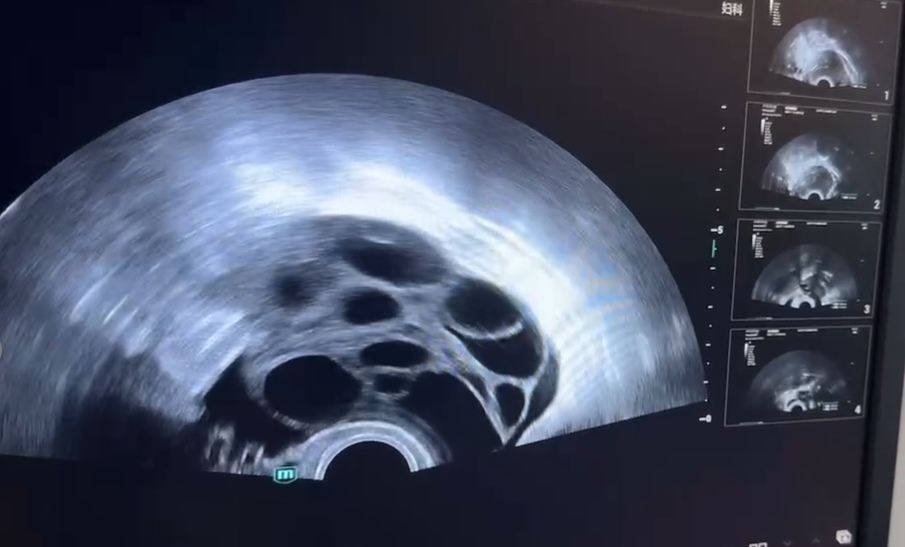

正常优势卵泡的超声图像特征:

· 直径超过10mm的卵泡被称为生长卵泡;

· 超过12mm的卵泡被称为优势卵泡;

· 超过18mm的卵泡则被视为成熟卵泡;

· 正常优势卵泡的直径范围通常在18至25mm之间,形态为圆形或椭圆形。

(促排后b超下的卵泡)